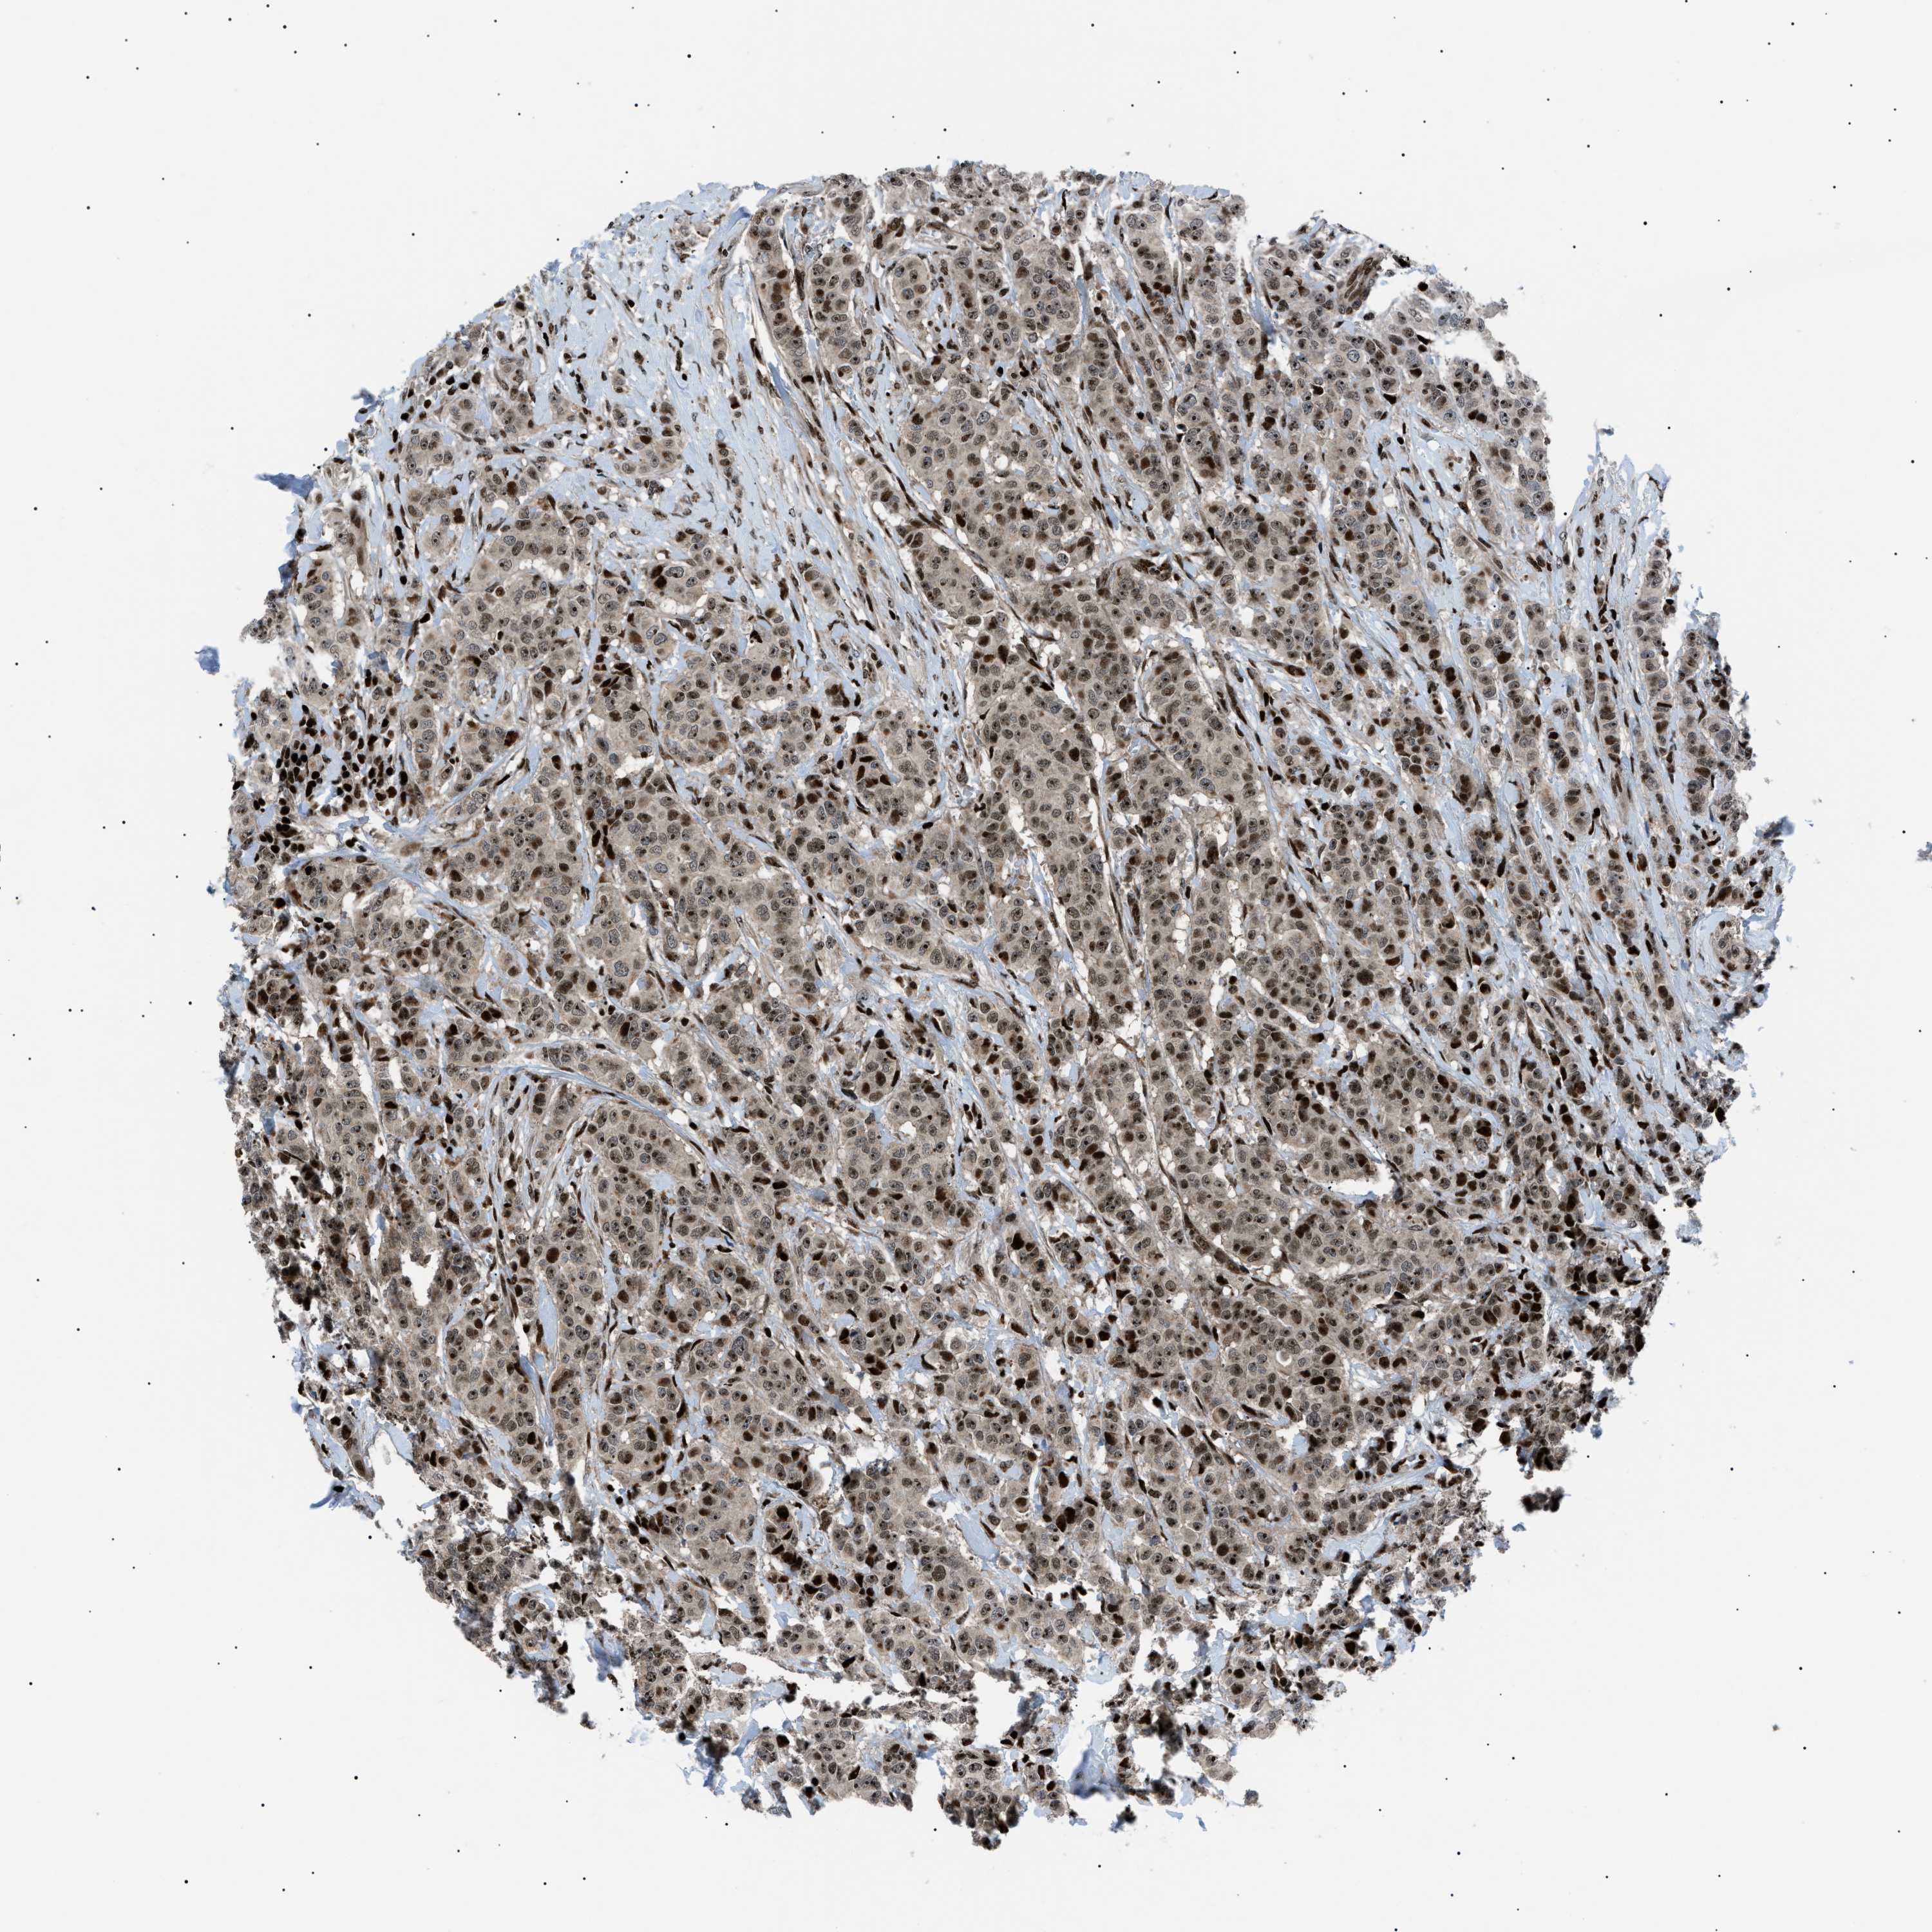

CANCER BREAST CANCER Show tissue menu

BRCA TCGA BRCA VALIDATION PROTEIN EXPRESSION

ANTIBODIES

AND

VALIDATION